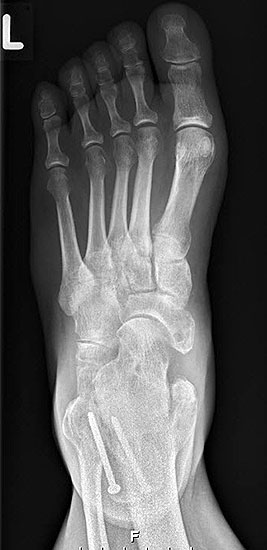

- Plantarflektierende Osteotomie / Arthrodese 1. Strahl

Die plantarflektierende Osteotomie des Os cuneiforme mediale wurde erstmalig von Cotton beschrieben und ist bei fixierter Vorfußsupination oder bei pathologischen seitlichen Talo-Metatarsale I Winkels indiziert (Abb. 11 a-i).

Radiologisches Beispiel einer fixierten Planovalgus Deformität Stadium III, 51 jähriger Patient. Stehendes präoperatives Röntgenbild und 1 Jahr postoperatives Röntgenbild des Fußes seitlich. Die Korrektur der Deformität umfaßte eine leicht korrigierende U

Abbildung 12

Eine fixierte Vorfußsupination sollte bereits präoperativ aber auch intraoperativ nach den bereits erfolgten o.g. Operationsschritten, insbesondere nach der Verlängerung der lateralen Säule, evaluiert werden. Nicht ganz so effektiv hinsichtlich Plantarflexion ist die proximale, plantarflektierende Osteotomie des Metatarsale I (oder I bis III).

Häufiger durchgeführt wird die plantarflektierende Osteotomie des Os cuneiforme mediale. Zwei Studien zeigen durchweg gute Korrekturergebnisse mit geringer Pseudarthroserate 54. Bei der Präparation kann es zu Verletzungen und später Neuromen kutaner Äste des N. saphenus und peroneus superficialis kommen. Weitere spezifische Komplikationen sind die Pseudarthrose und störende Implantate.